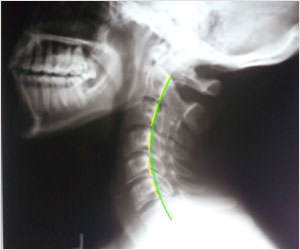

Neck pain almost always has an underlying postural correlation. Poor posture strains your neck muscles and stresses and/or misaligns your spine which can result in pain, creating acute or chronic issues requiring treatment.